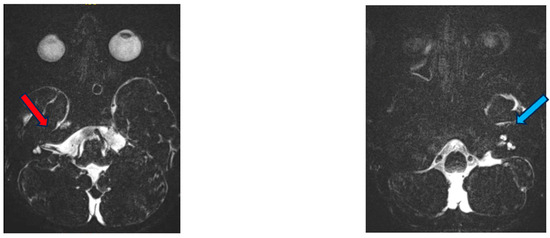

3.1. Case 1

3.2. Case 2